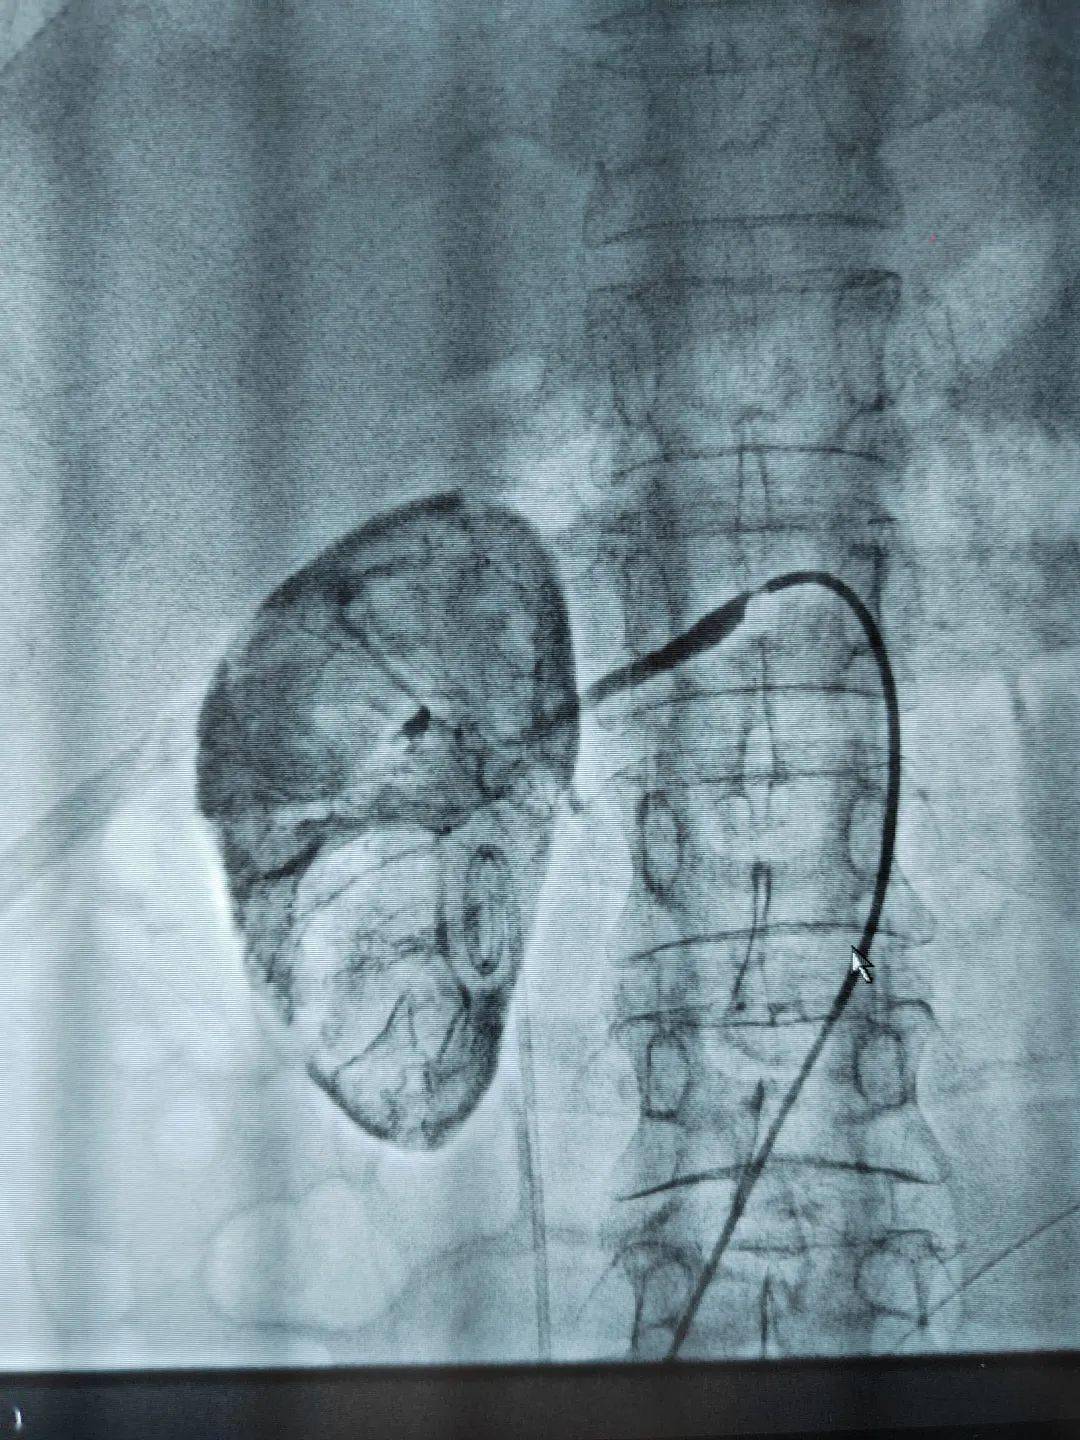

大同市第五人民医院介入科行肾动脉支架植入实例分享

右肾动脉支架植入后造影显示

双肾动脉造影